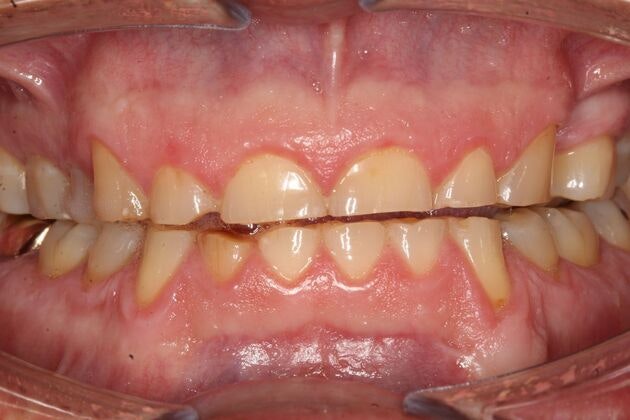

A smile has an incredible influence not only on how you are perceived by others, but how you perceive yourself. A healthy, beautiful mouth is much more than simply straight, white teeth. It involves a proper bite relationship (occlusion), joint and muscle comfort (TMJ), and proper soft tissue (gum) health. Our Vernon and Coventry, CT, dentists are dedicated to providing cosmetic dentistry and restorative procedures that can restore your smile to optimum health and appearance.